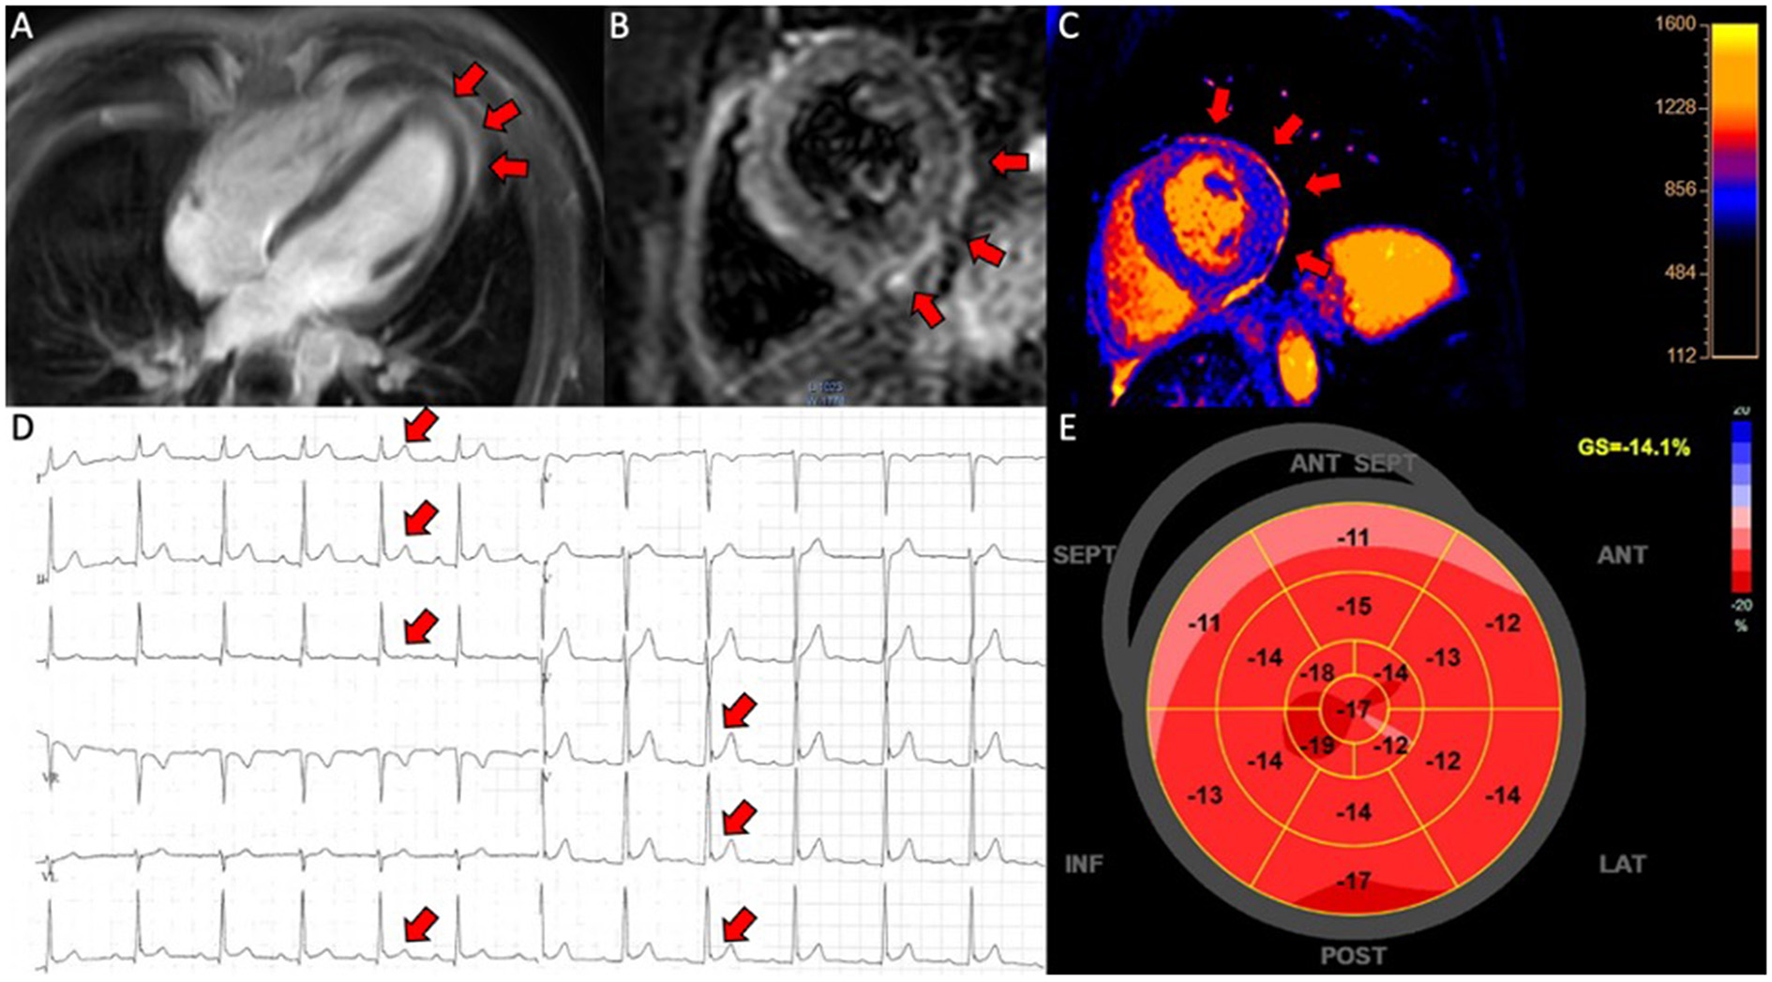

Figure 2

Pericarditis in a patient (case 9). (A) CMR, late gadolinium enhancement in the pericardium in 4-chamber view; (B) CMR, short axis T2-weigthed image showing hyper-intensive signal in the pericardium indicative of oedema; (C) CMR, T1-map in short axis showing increased T1 values up to 1,231 ms in the pericardium; (D) electrocardiogram showing ST-elevations in lead I, II, III, aVF and V4-V6; (E) 17-segment plot of global longitudinal strain on echocardiography with decreased values in the basal segments anteriorly.